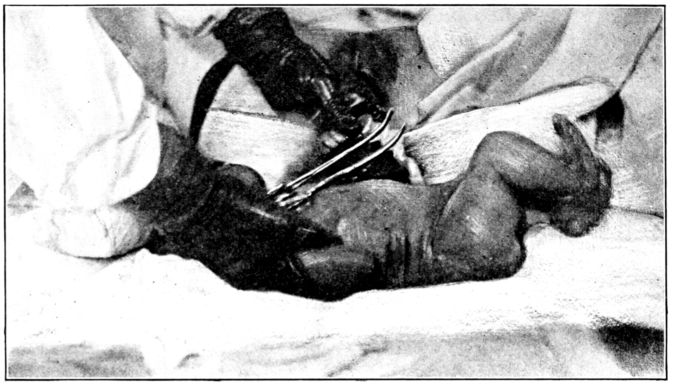

| 155. | Preparation for circumcision | 468 |

| 156. | Baby draped with sterile sheet, in above | 469 |